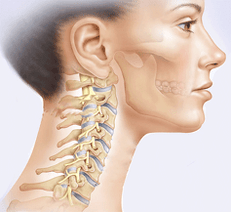

Hoại tử xương cổ là loại bệnh nguy hiểm nhất. Cột sống cổ bao gồm bảy đĩa đệm và là phần di động nhất của cột sống, mang lại khả năng nghiêng và quay đầu. Anh ta có một chiếc áo nịt ngực cơ bắp tương đối yếu. Đồng thời, sự mất ổn định của cột sống cổ kết hợp với hoạt động thể chất liên tục (nhu cầu hỗ trợ đầu, kiểm soát việc quay và uốn cong) giải thích tính nhạy cảm cao của phần cột sống này đối với cả chấn thương và các thay đổi thoái hóa, về cơ bản là thoái hóa xương khớp.

Vùng cổ nhỏ chứa nhiều ống thần kinh và mạch máu cung cấp cho não. Ở vùng cổ, các đốt sống khít chặt vào nhau hơn. Vì vậy, ngay cả với

Một thay đổi nhỏ ở một trong các đốt sống có thể gây chèn ép hoặc dịch chuyển dây thần kinh và mạch máu.

Một thay đổi nhỏ ở một trong các đốt sống có thể gây chèn ép hoặc dịch chuyển dây thần kinh và mạch máu.Do rối loạn tuần hoàn não, đau nửa đầu, loạn trương lực cơ thực vật và tăng huyết áp, các vấn đề về hệ tim mạch và hô hấp, thính giác, thị giác và phối hợp xảy ra. Ở dạng tiến triển, thoái hóa đốt sống cổ có thể dẫn đến hội chứng động mạch đốt sống. Động mạch đốt sống cung cấp máu cho hành não và tiểu não. Khi động mạch bị nén, tình trạng thiếu máu não và tủy sống có thể phát triển và đột quỵ cột sống có thể xảy ra.

Thoái hóa đốt sống cổ dẫn đến tổn thương rễ thần kinh - hình thành các khối u trên đốt sống, mất khả năng vận động một phần hoặc toàn bộ. Hậu quả nghiêm trọng nhất của thoái hóa đốt sống cổ là chèn ép tủy sống, có thể gây tử vong. Những hậu quả nghiêm trọng có thể tránh được nếu bệnh được điều trị kịp thời.